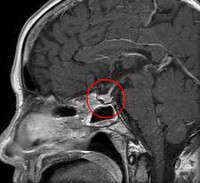

С целью функционального обследования щитовидной железы определяются гормональные показатели (Т4 св. ТТГ), проводится УЗИ щитовидной железы. При подозрении на поражение почек исследуются клинические анализы крови и мочи, биохимические показатели (электролиты). С целью оценки плотности костной ткани выполняется денситометрия. Для определения причин гиперпролактинемии (главным образом, выявления аденом гипофиза), проводится рентгенография черепа, КТ или МРТ головного мозга или гипоталамо-гипофизарной области.